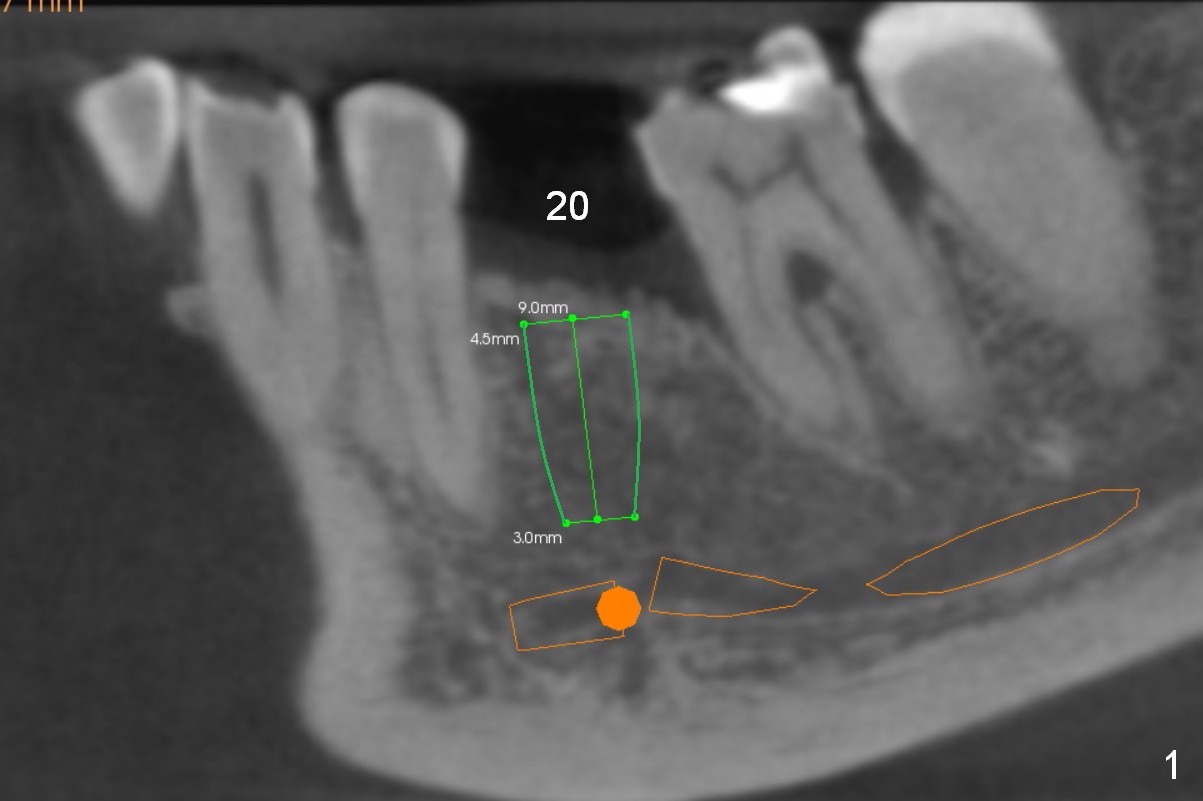

Low Density at Cancellous Bone

As a part of project converting the lower partial denture into implant-supported restoration, an implant will be placed at #20 (Fig.1,2). Since bone density at the cortex and the medulla is 800 and 200 units, Marking drill will be used to start osteotomy (2 mm in depth) to pass through the cortex, while Magic osteotomes are to be used to extend osteotomy to 9 mm (bone condensation).